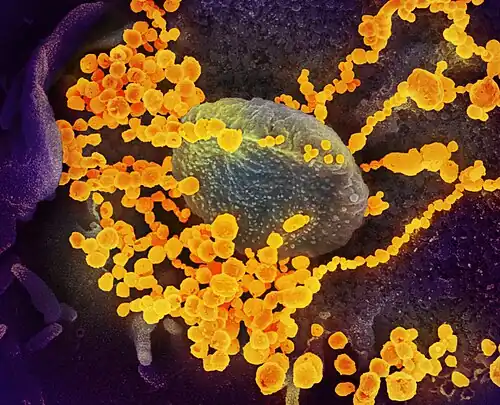

Selected image –